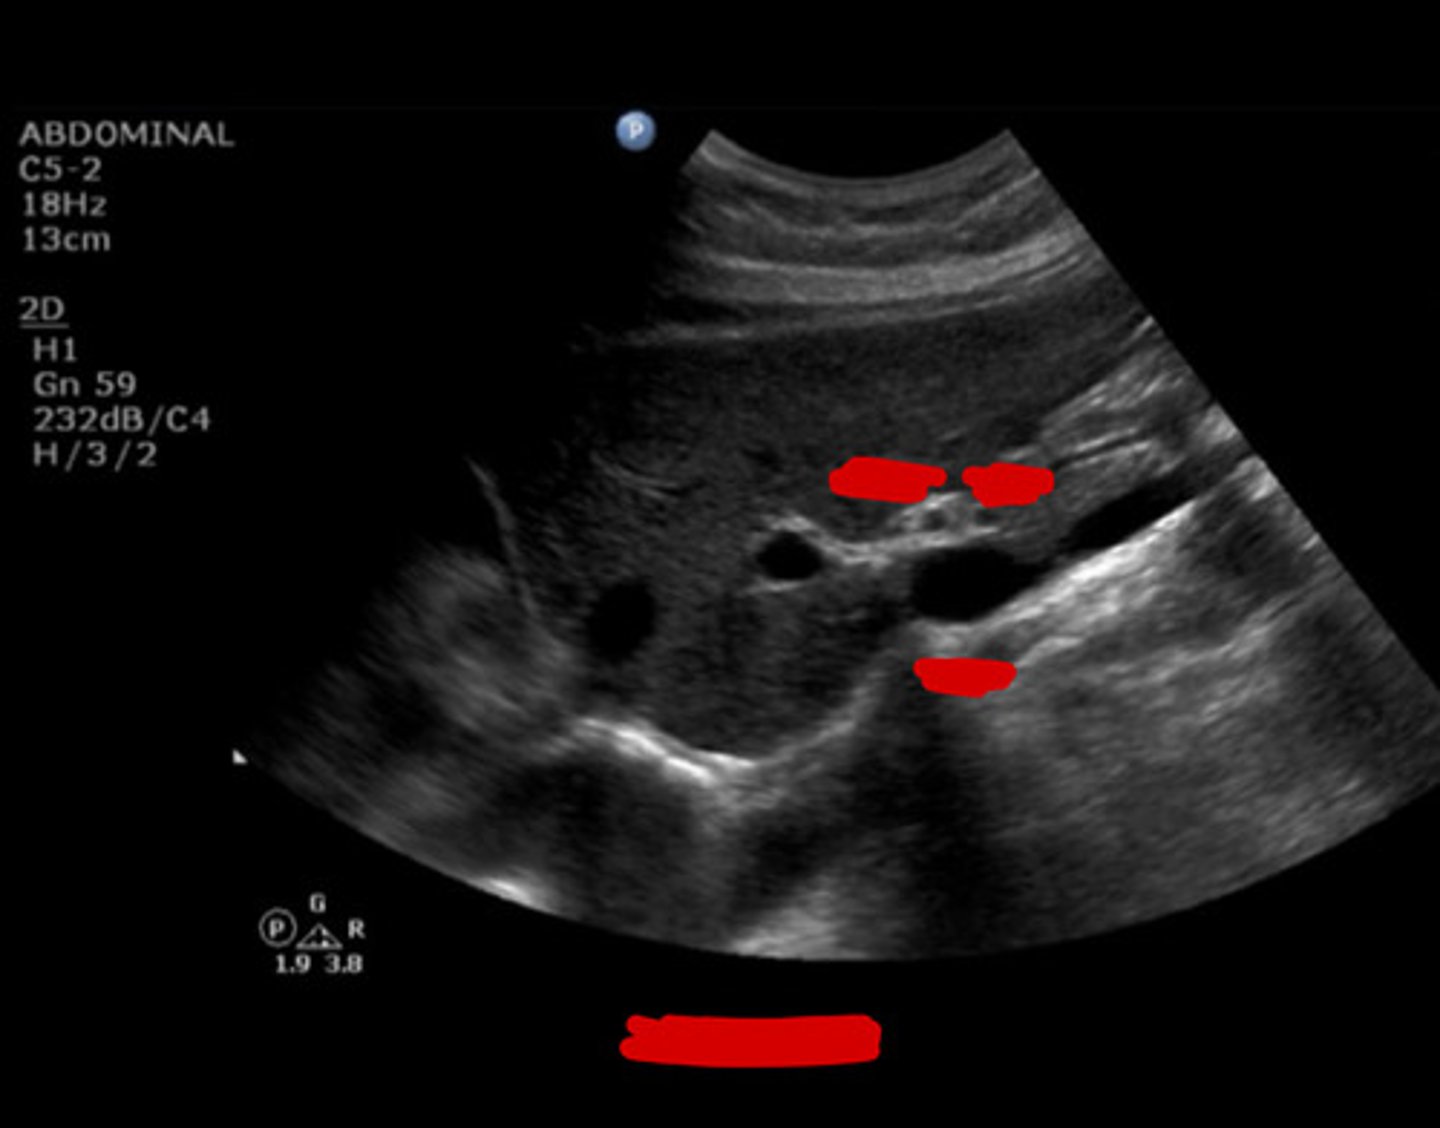

12

New cards

HA

Identify the following;

<p>Identify the following;</p>

13

MPV

14

Anterior

The common bile duct (CBD) runs where in relation to the portal vein?